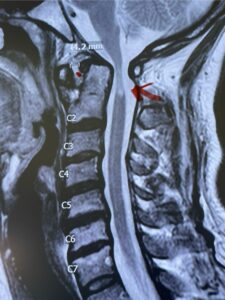

This is a 42 year-old female who presents with severe progressive weakness and numbness and difficulty with balance over a 6-month period. She has a history of having a motor vehicle accident at 5 years old but was never imaged. On exam she was noted to be severely myelopathic. Imaging revealed severe spinal cord compression at the level of C1 (Figs 4a and b).

Fig. 4a: Sagittal T2-weighted cervical MRI demonstrating severe cord compression with myelomalacia of upper cervical spinal cord (red arrow). Notice the increased atlanto-dens interval (red dot).

Fig. 4b: Axial T2-weighted cervical MRI demonstrating severe spinal cord compression from atlanto-axial instability (red arrow)